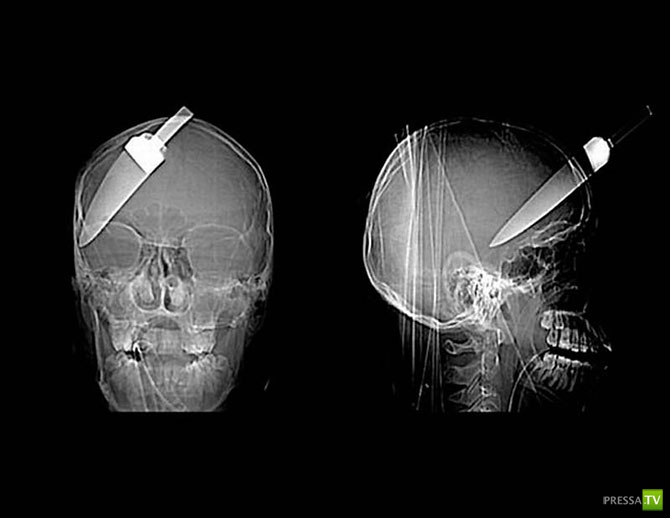

Нож в голове 10-летнего мальчика. Мальчик выжил.